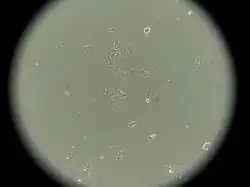

MCF-7 is a breast cancer cell line isolated in 1970 from a 69-year-old woman.[1] MCF-7 is the acronym of Michigan Cancer Foundation-7, referring to the institute in Detroit where the cell line was established in 1973 by Herbert Soule and co-workers.[2] The Michigan Cancer Foundation is now known as the Barbara Ann Karmanos Cancer Institute.[3]

MCF-7 cells have the following characteristics:[2][6][7][9][10][11]

- Primary tumor (invasive breast ductal carcinoma)

- Originate from pleural effusion

- Estrogen receptors present[12]

- Proliferative response to estrogens

- Presence of progesterone receptors

- Contains 17β-estradiol-binding protein[8]

- Cannot have ERBB2 gene amplification (with Her2/neu protein overexpression)

- Tumorigenic in mice but only with estrogen supplementation if engrafted into the subcutaneous fat or mammary fat pad

- Tumorigenic in mice without estrogen supplementation if engrafted intraductally[13]

- Luminal epithelial phenotype

This cell line retained several characteristics of differentiated mammary epithelium, including the ability to process estradiol via cytoplasmic estrogen receptors and the capability of forming domes.